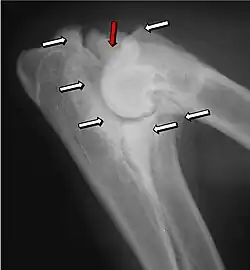

Na osteocondrite dissecante, o período normal de mudança de cartilagem para ósso no desenvolvimento da articulação falha ou está atrasada. A cartilagem continua a crescer e pode partir-se ou tornar-se necrótica. A causa é incerta, mas, possivelmente, inclui a genética, traumas e nutrição (incluindo o excesso de cálcio e diminuição da Vitamina C).[4] As lesões por osteocondrite dissecante são encontradas no cotovelo no epicôndilo medial do úmero. Condições específicas relativas à osteocondrite dissecante incluem a fragmentação do processo medial coronoid process da ulna e um ununited anconeal process da ulna. Todos os tipos de osteocondrite dissecante do cotovelo são geralmente encontrados em cães de raças grandes, com sintomas à partir dentre as idades de 4 a 8 meses. Os machos são afetados duas vezes mais frequentemente que as fêmeas. A doença geralmente afeta ambos os cotovelos (30 a 70% das vezes), e os sintomas incluem claudicação intermitente, inchaço das articulações, e rotação externa e abdução da pata.[5] Osteoartrite irá se desenvolver mais tarde na maioria dos casos.

Ununited anconeal process é causado pela separação da ulna do centro de ossificação do processo anconeal.[6] Processo medial coronoid process da ulna é causado por uma falha do coronoid process para unir-se com a ulna. Osteocondrite dissecante do epicôndilo medial do úmero é causada por distúrbios endocondral de fusão da epífise do epicôndilo medial, com a extremidade distal do úmero, que por sua vez, pode ser causado por avulsão da epífise.[7]